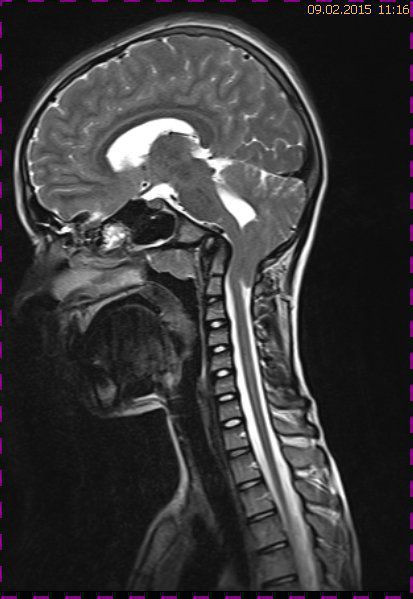

Abb. 3.1 T2 TSE sagittal: progrediente intraspinale Tonsillendislokation mit nachweisbarem Ödem des Zervikalmarks in Höhe von HWK 2

Abb. 3.2 T2 TIRM: das intramedulläre Ödem wird durch die Tonsillenkompression reproduzierbar dargestellt, betonter Zentralkanal des Halsmarks

Abb. 3.3 T2 TSE transversal: keine intraventrikuläre Drucksteigerung, keine Zeichen einer Liquordiapedese

Bei dieser Untersuchung wurde übersehen, dass die Kleinhirntonsillen in das Foramen magnum disloziert waren und eine Arnold-Chiari-Malformation mit Erweiterung des 4. Ventrikels und des Aquäduktes inklusive Kleinhirntonsillentiefstand vorlag. Bei zwischenzeitlich auswärtig erfolgtem CT der HWS wurde eine Anlagestörung im kraniozervikalen Übergang beschrieben. Eine Kontrolluntersuchung des Kopfes weitere 4 Monate später dokumentierte neben einem medullären Ödem einen progredienten Tonsillentiefstand, der zur neurochirurgischen Behandlung mit operativer Erweiterung des Foramen magnum führte.